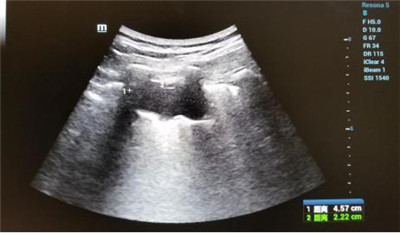

患者郑女士,在乐鱼手机站入口被确诊肺癌,癌肿位于左肺下叶近胸膜处,大小约4.5x2.2cm,经化疗后肿块变化不明显。肿瘤外科二病区王雅辉副主任医师与超声科刘晓晖主任医师会诊后,认为可以为患者施行超声引导下肺癌微波消融术,因为属于首例,特邀西京医院王建宏教授进行术中指导,超声科华玺主治医师进行引导,麻醉手术科李万鹏副主任进行术中监测,降低手术风险,提高肿瘤综合治疗效果。整个治疗过程约30分钟,患者术中术后生命体征平稳。

超声造影评估微波消融治疗情况